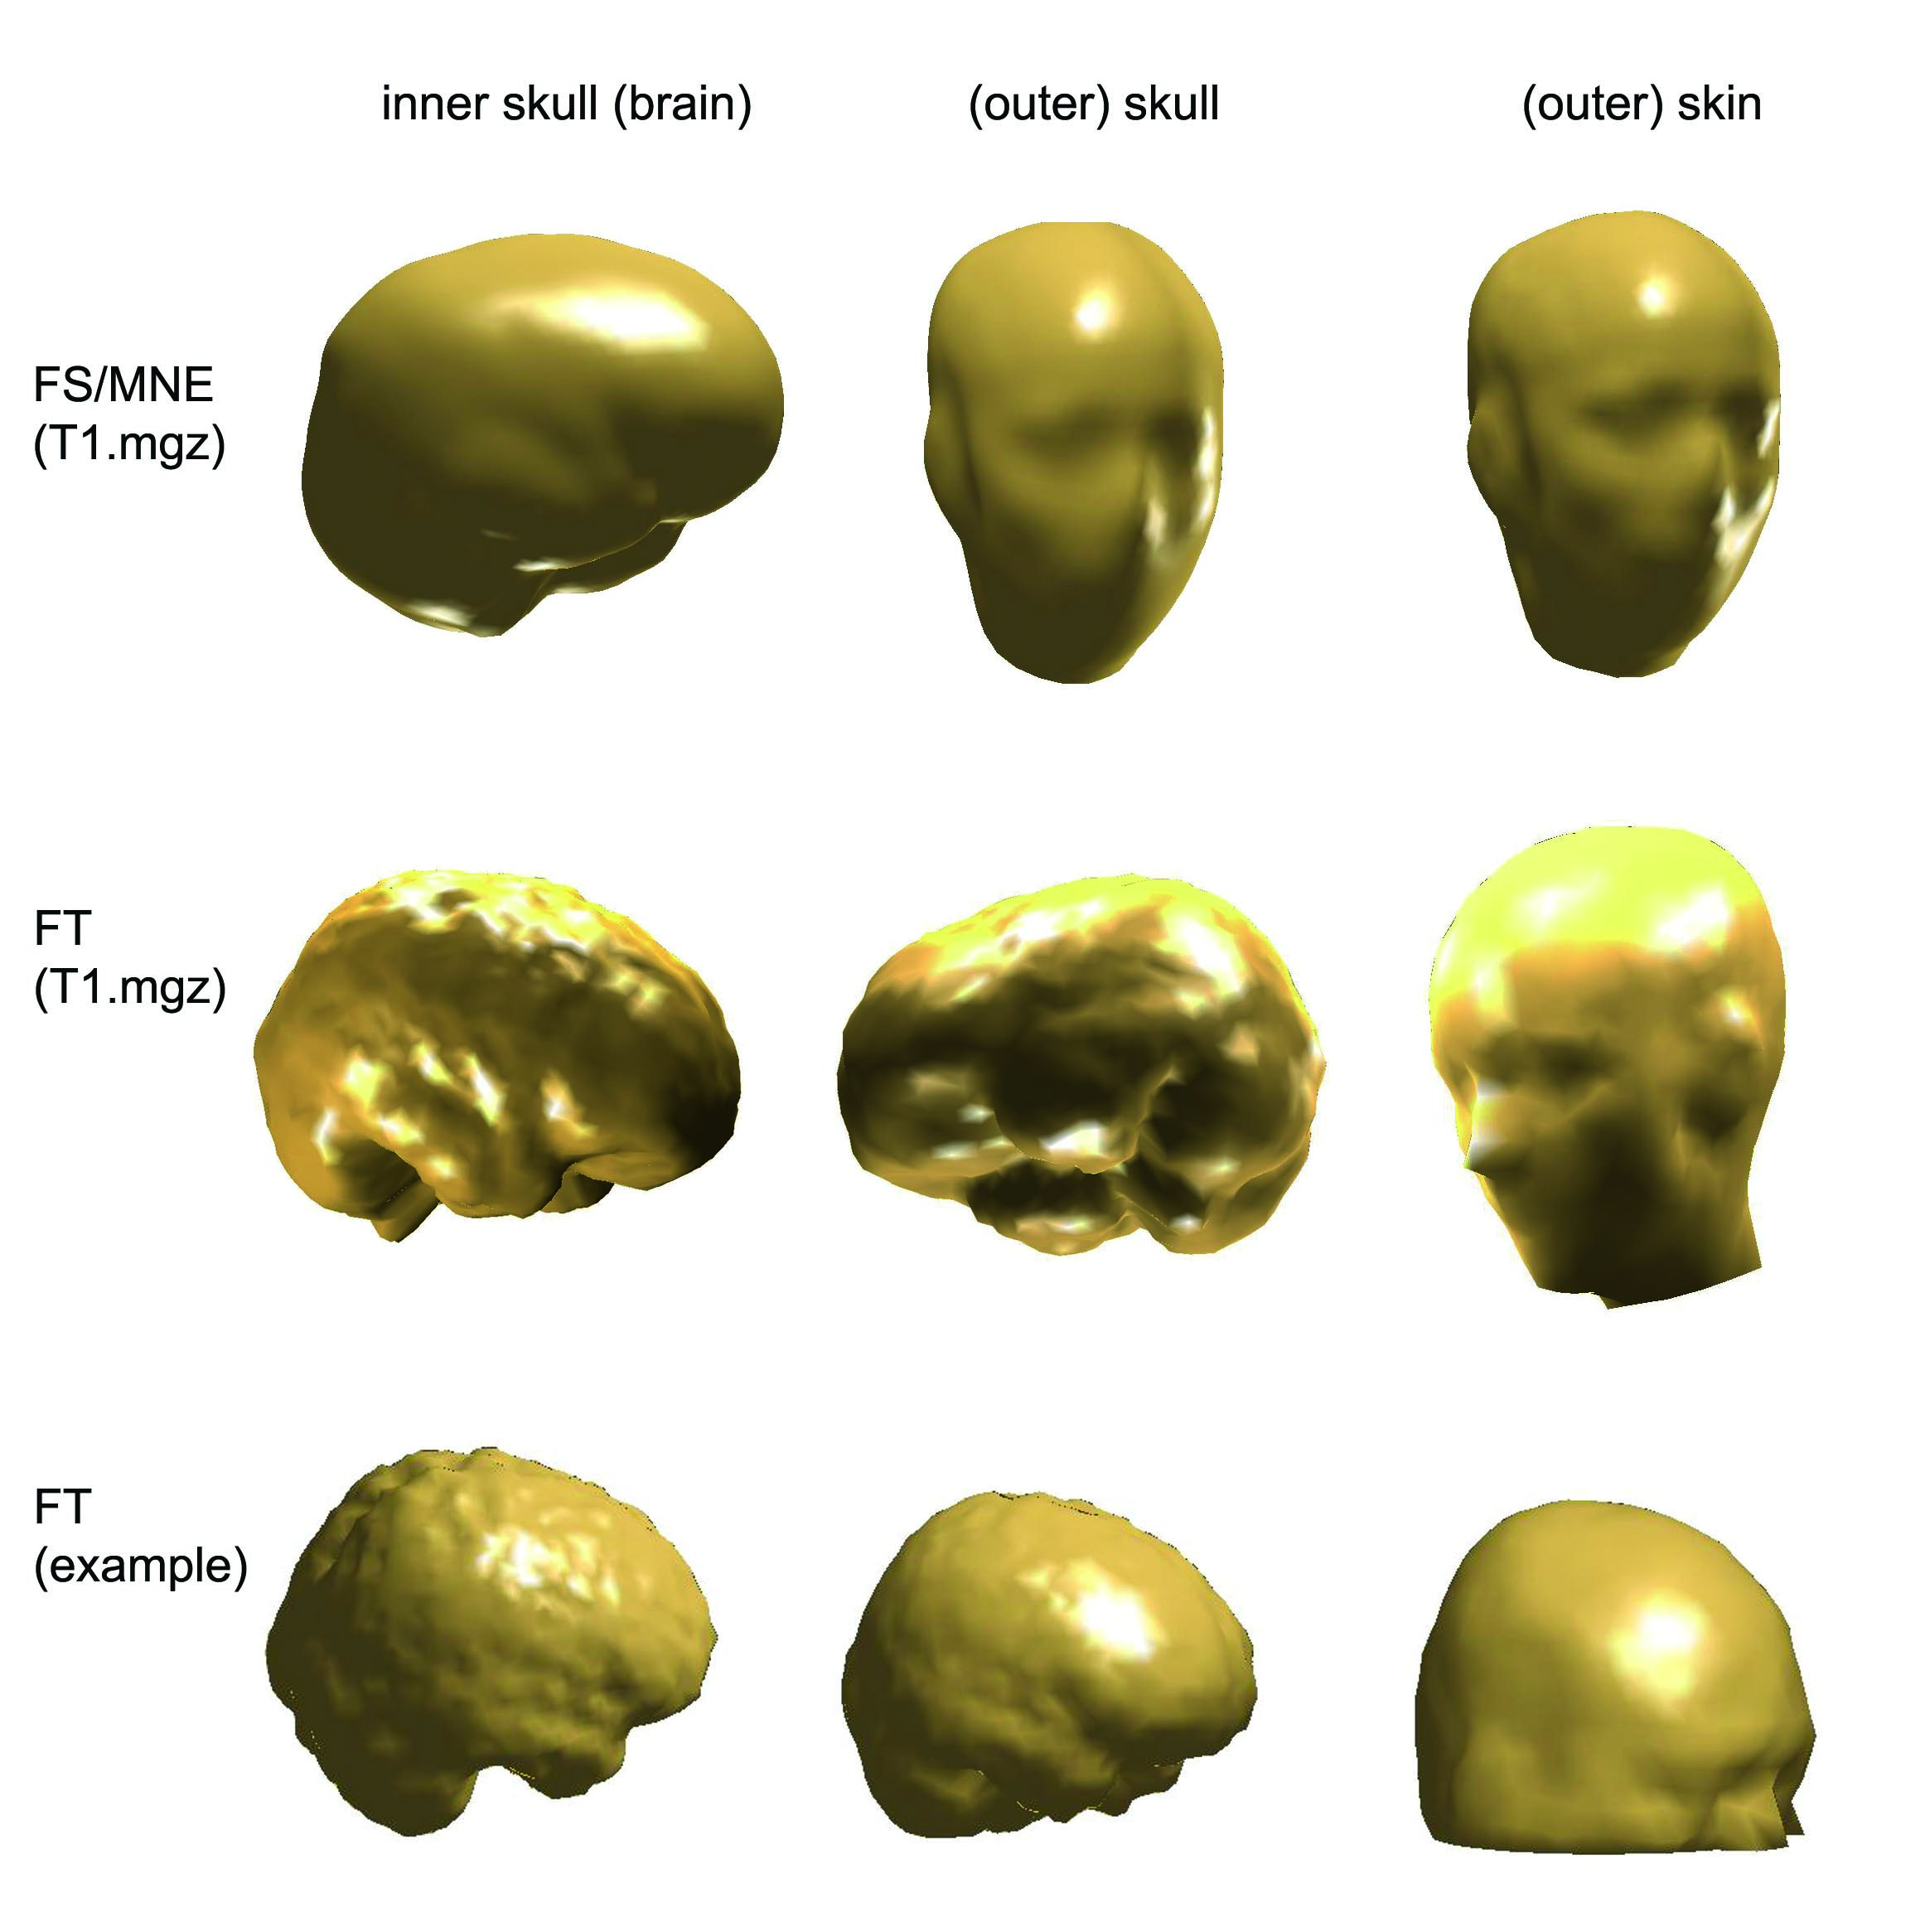

Comparing BEM meshes

I have created BEM meshes in three way

- I have the BEM meshes created by FreeSurfer

- I have created BEM meshes with FieldTrip, using the same T1.mgz volume that FS used for creating meshes. (It is a conformed (256x256x256) volume with intensity normalization.)

- I have created BEM meshes with FieldTrip, using a .mnc volume (downloaded from internet). This sort of volume was used also in the tutorial example script of FieldTrip.

I could read in the FS/MNE BEM meshes in F

innerskull = ft_read_headshape('$SUBJECTS_DIR/<subject's name>/bem/<subject's name>-inner_skull-5120.surf');

This is the code for plotting a mesh that was created by FS/MN

ft_plot_mesh(innerskull,'facecolor','skin');camlight;

And this is for plotting a mesh (inner skull) created by F

ft_plot_mesh(vol.bnd(3),'facecolor','skin');camlight;

The following picture show the BEM meshes